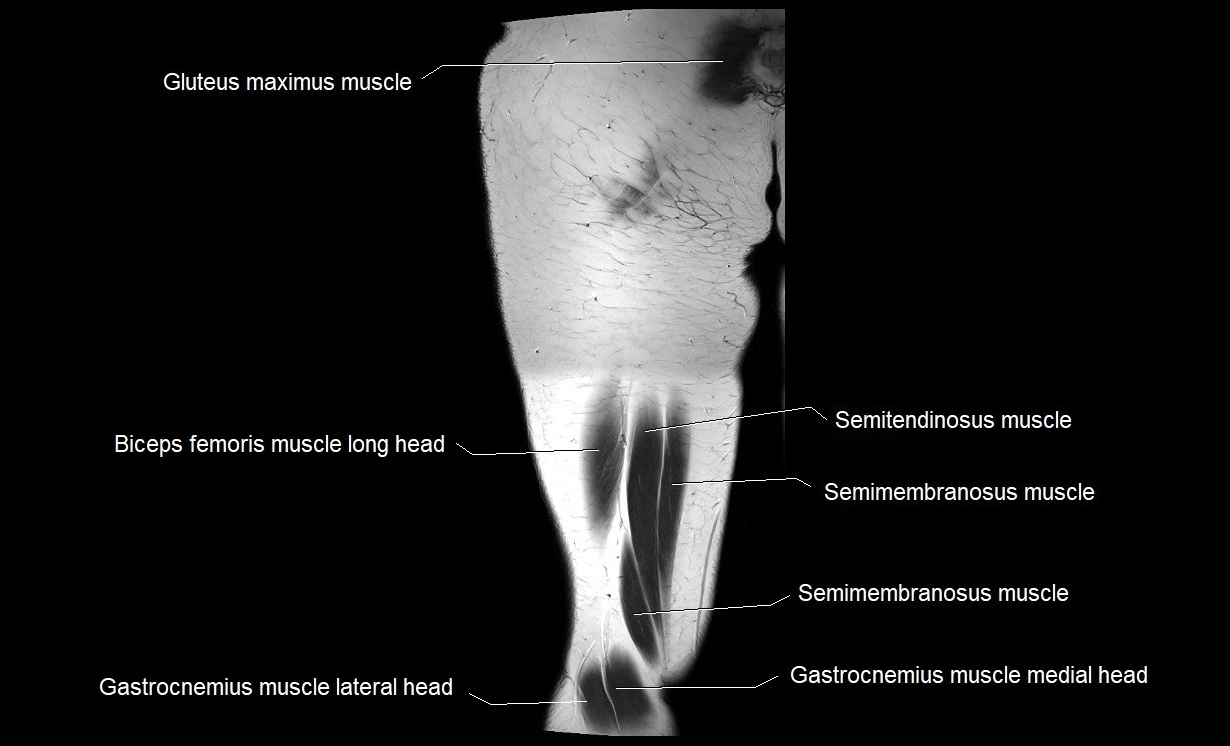

- Gluteus maximus muscle

- Biceps femoris muscle (Long head)

- Semimembranosus muscle

- Semitendinosus muscle

- Gastrocnemius muscle